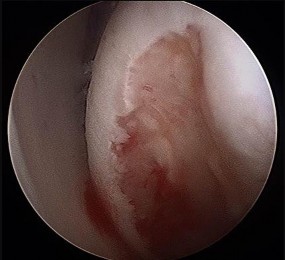

Which image seen during arthroscopic treatment is most likely associated with this patient’s condition?

An otherwise healthy 31-year-old man has had right knee pain for the past 9 months. His former physician

administered a cortisone injection and ordered 6 months of physical therapy. The patient later had an arthroscopy with debridement of the right knee by another physician and completed another course of physical therapy. The patient received minimal relief from these treatments and still is not able to walk longer distances or go on hikes. On examination, he is a healthy appearing male with a body mass index of 24 kg/m2. He has a small effusion, minimal quadriceps atrophy, no tenderness about the knee, full range of motion, stable to varus and valgus stress at 30° of flexion, a grade 1 Lachman test, and a normal posterior drawer. Figures 1 through 4 are his arthroscopic views, radiograph and MRI scan from his prior surgical procedure. What is the next most appropriate step in treatment?